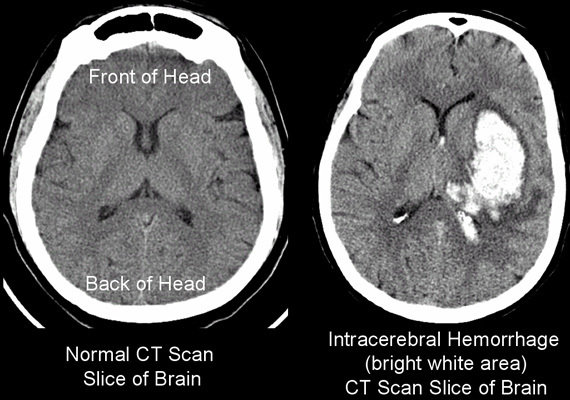

Hemorrhage

- Blood vessels in the brain leak or rupture, putting pressure on the brain

Types of Hemorrhage Strokes:

- Intracerebral hemorrhage

- Occurs inside the brain

- Subarachnoid hemorrhage

- Occurs in the space between the brain and skull

- Usually from a brain aneurysm